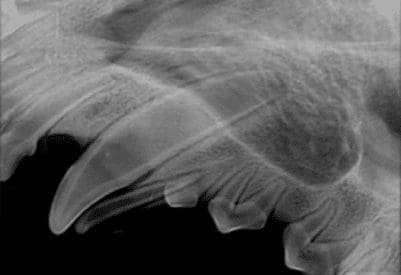

Fig 1. Assessment of retained deciduous canine using dental radiography.